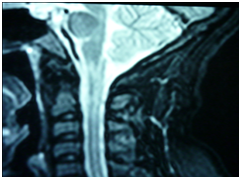

Figure 1 T2 weighted hyperintense lesions in upper cervical region.

A 26-year-old woman had 2 episodes of Right Optic Neuritis 1 year apart where there was a partial resolution after intravenous steroids. She had 1 episode of tetraplegia, which improved after 2 months without any treatment.  Clinically, there was evidence of Right Optic atrophy and no other cranial nerve deficit. Left hemiparesis with upper motor neuron deficit was noted and the right upper and lower limbs were normal. No features of connective tissue disease were seen clinically nor were there and blood investigations supporting any other autoimmune disease. Anti-Aquaporin 4 antibody was negative. MRI Brain on February 2012 was normal. However, MRI Spine showed patchy intramedullary lesion extending from C5-T2 seen in central and dorsal aspect. A Repeat MRI done in February 2013 revealed high signal intensity in right corpus callosum, thalamus, corona radiata, lentiform nucleus, insula, cerebral peduncle. Similar lesions were seen in midbrain, medulla oblongata Figure 1. A diagnosis of Multiple sclerosis and a differential of Neuromyelitis Optica Spectrum of Disorder were being considered. She was scheduled a clinic appointment to discuss diagnosis and treatment options. No treatment had been commenced yet. However, she developed sudden onset of shortness of breath while at home and died in the ambulance on the way to the hospital. As the patient was not seen by any physician there were no formal clinical assesment and diagnosis were given for her symptom.